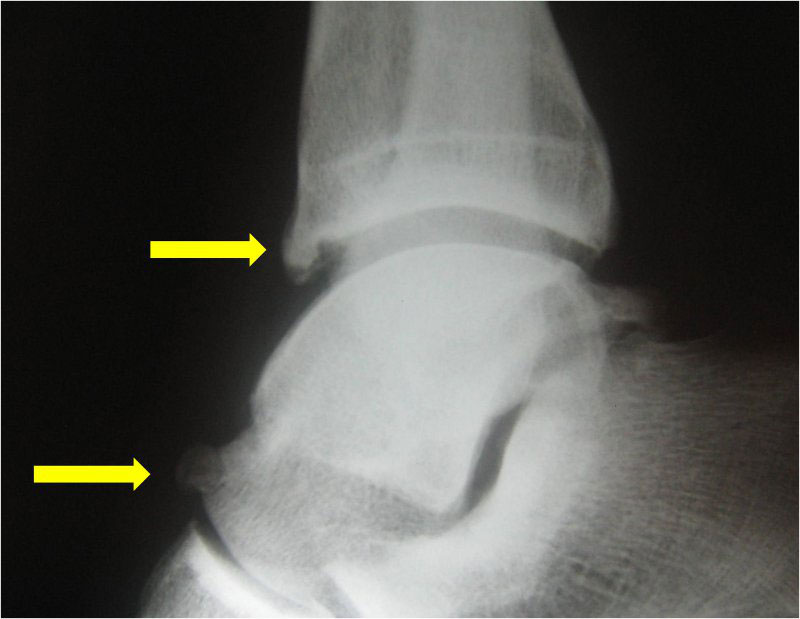

По МРТ и на рентгенограммах импинджмент голеностопного сустава.

Пациенту обязательно назначают рентгенограмму. На рентгенологическом снимке доктор легко увидит остеофиты – костные разрастания, появившиеся из-за воспалительного процесса. Дополнительно выполняется снимок в стрессовом положении. На нем доктор определит, есть ли соударение костей.

МРТ для диагностики недуга не является обязательным исследованием. Его выполнение рекомендуется, если необходимо провести дифференциальную диагностику с другими патологиями либо в начальных стадиях патологии.